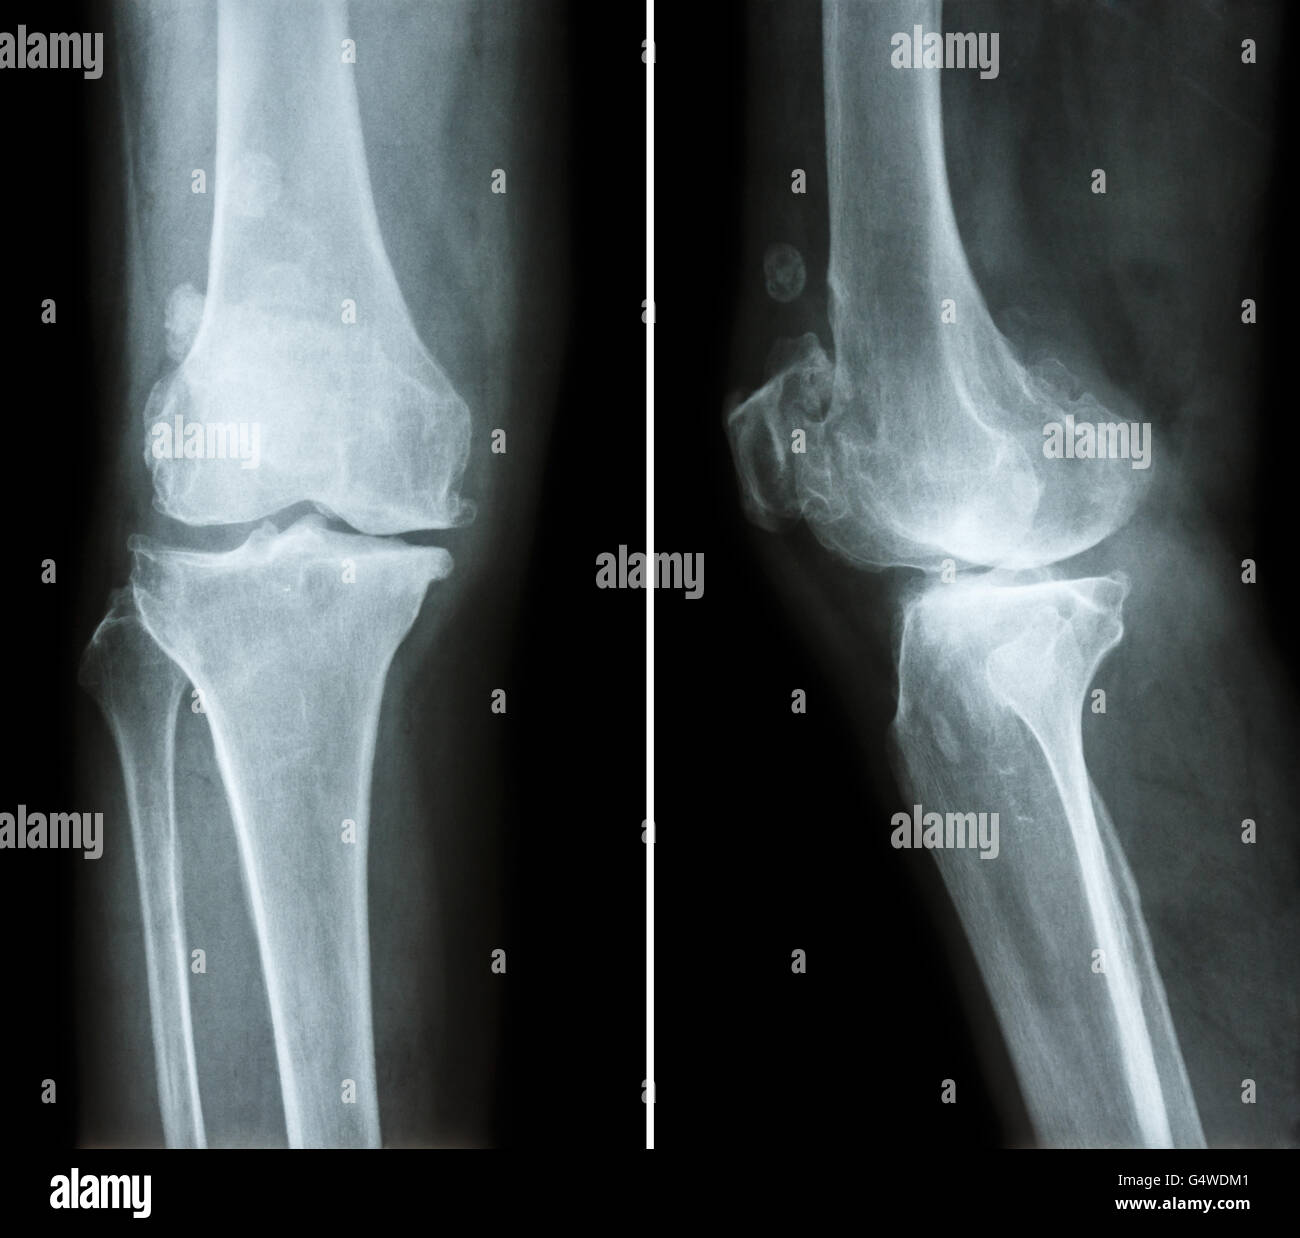

L'arthrose du genou . film x-ray ( genou - antérieure et postérieure vue latérale ) montre l'espace mixte étroit éperon ) , ('ostéophyte Banque D'Imageshttps://www.alamyimages.fr/image-license-details/?v=1https://www.alamyimages.fr/photo-image-l-arthrose-du-genou-film-x-ray-genou-anterieure-et-posterieure-vue-laterale-montre-l-espace-mixte-etroit-eperon-osteophyte-106280385.html

L'arthrose du genou . film x-ray ( genou - antérieure et postérieure vue latérale ) montre l'espace mixte étroit éperon ) , ('ostéophyte Banque D'Imageshttps://www.alamyimages.fr/image-license-details/?v=1https://www.alamyimages.fr/photo-image-l-arthrose-du-genou-film-x-ray-genou-anterieure-et-posterieure-vue-laterale-montre-l-espace-mixte-etroit-eperon-osteophyte-106280385.htmlRFG4WDM1–L'arthrose du genou . film x-ray ( genou - antérieure et postérieure vue latérale ) montre l'espace mixte étroit éperon ) , ('ostéophyte